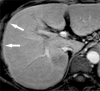

Gadolinium ethoxybenzyl diethylenetriamine pentaacetic acid (Gd-EOB-DTPA; Gadoxetic acid; Gadoxetate disodium) is a hepatocyte-specific MR contrast agent. It acts as an extracellular contrast agent in the early phase after intravenous injection, and then is taken up by hepatocytes later. Using this contrast agent, we can evaluate the hemodynamics of the liver and liver tumors, and can therefore improve the detection and characterization of hepatocellular carcinoma (HCC). Gd-EOB-DTPA helps in the more accurate detection of hypervascular HCC than by other agents. In addition, Gd-EOB-DTPA can detect hypovascular HCC, which is an early stage of the multi-stage carcinogenesis, with a low signal in the hepatobiliary phase. In addition to tumor detection and characterization, Gd-EOB-DTPA contrast-enhanced MR imaging can be applied for liver function evaluation and prognoses evaluation. Thus, Gd-EOB-DTPA plays an important role in the diagnosis of HCC. However, we have to employ optimal imaging techniques to improve the diagnostic ability. In this review, we aimed to discuss the characteristics of the contrast media, optimal imaging techniques, diagnosis, and applications.